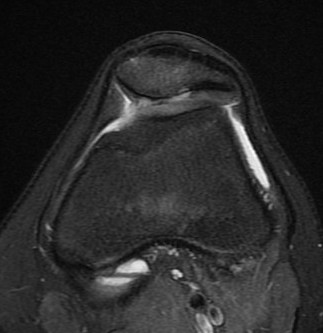

MRI

Lateral subluxation / trochlea dysplasia

Articular cartilage damage

TTTG